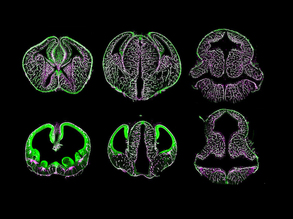

Bloody Brains